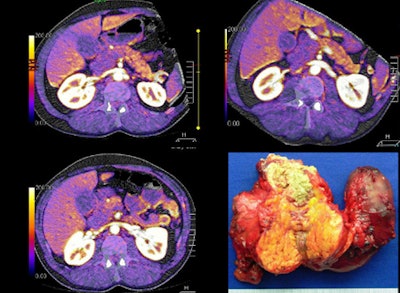

![]()  |

| Large pancreatic mass and head are visible at perfusion CT, with surgery specimen for comparison. |